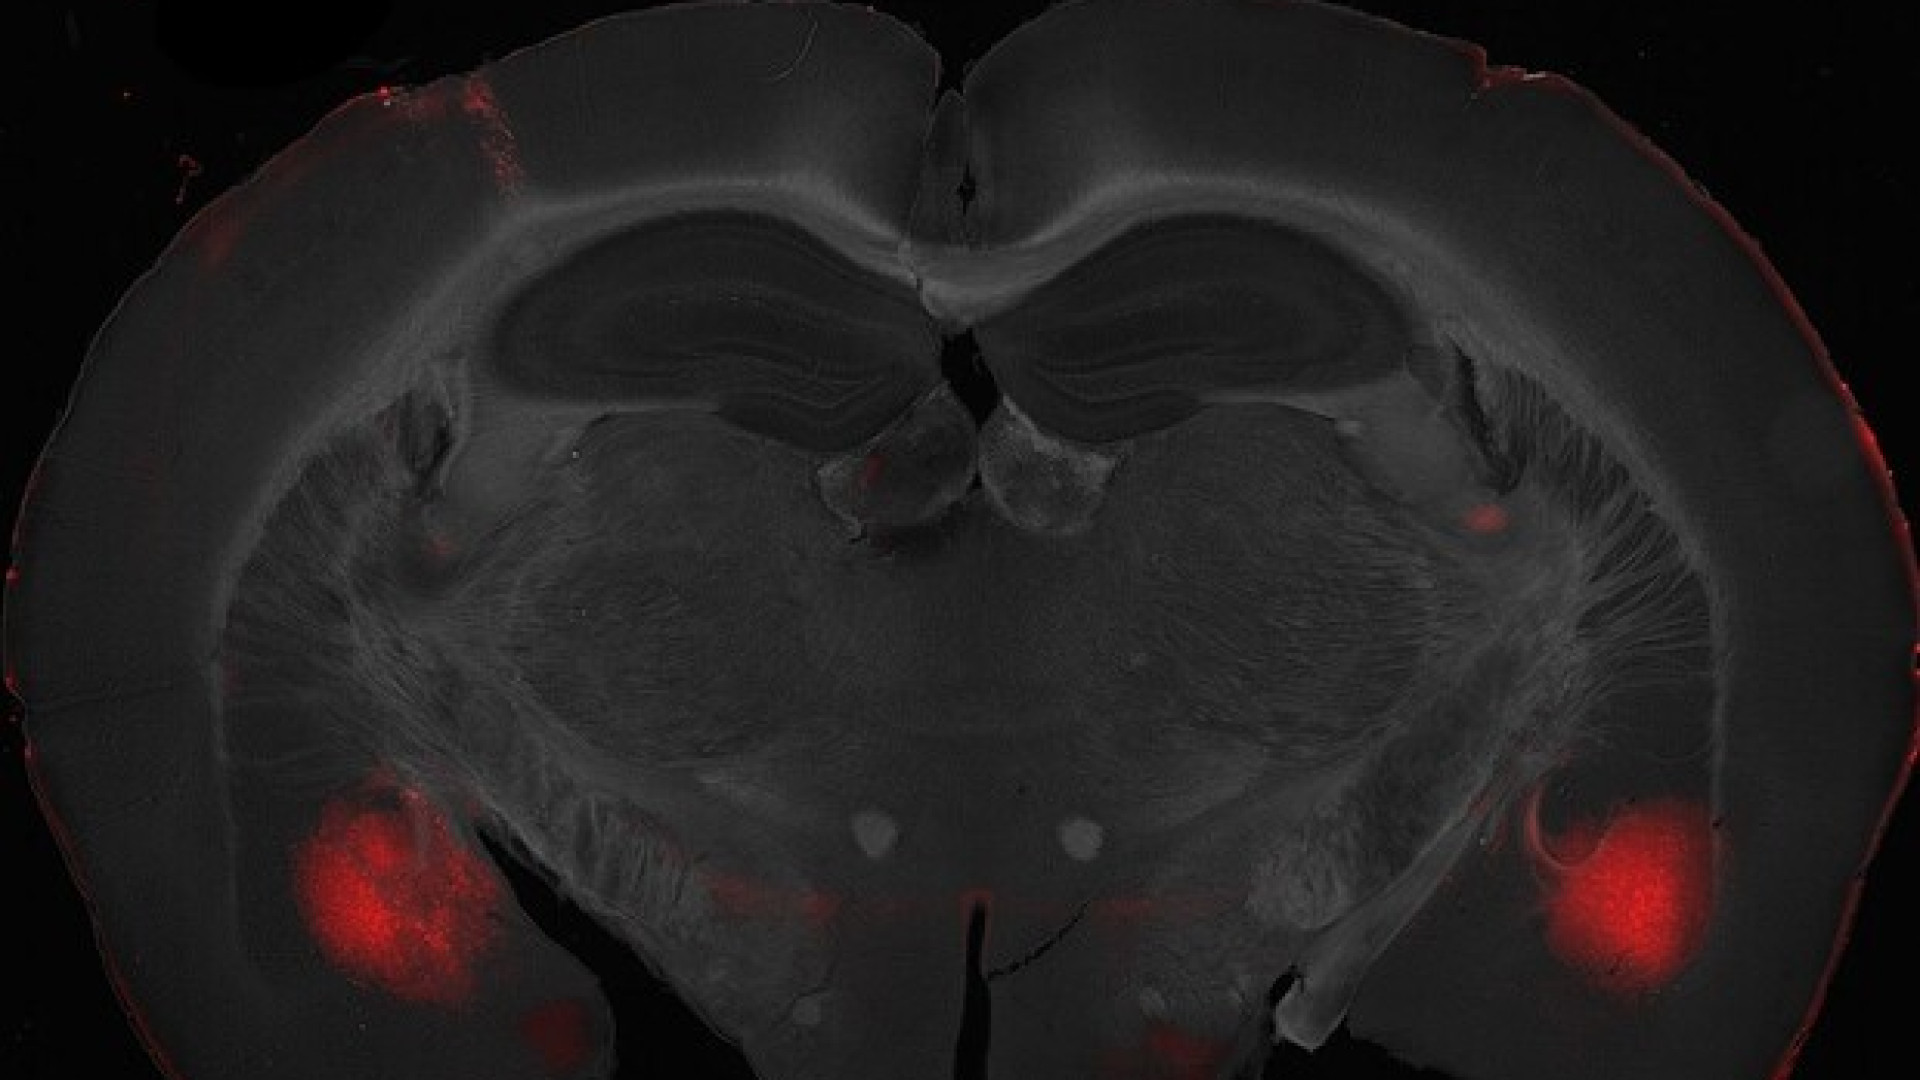

A modulare il comportamento verso gli altri è un circuito nervoso del cervello che collega il centro delle emozioni, ovvero l’amigdala baso laterale, con la regione delle decisioni, la corteccia prefrontale.

Lo dimostra uno studio sui topi condotto dai ricercatori dell’Università Statale di Milano e dell’Istituto italiano di tecnologia (Iit).

“La corteccia prefrontale e l’amigdala baso laterale lavorano come un’orchestra nel modulare le nostre scelte altruistiche o egoistiche: lo abbiamo scoperto grazie alla chemogenetica, che attraverso l’uso di molecole permette di attivare e disattivare in maniera precisa singoli circuiti cerebrali”, spiega Diego Scheggia, il neuroscienziato che ha condotto lo studio tra Iit e la Statale di Milano.

“Quando abbiamo spento i neuroni della corteccia che proiettano i loro impulsi sull’amigdala, i topi hanno mostrato comportamenti egoisti, rifiutandosi di condividere il cibo coi loro compagni di gabbia. Al contrario, spegnendo i neuroni che dall’amigdala inviano segnali alla corteccia, abbiamo riscontrato alterazioni dell’apprendimento: i topi faticavano a capire le conseguenze delle loro azioni e assumevano comportamenti egoisti o altruisti in maniera casuale”.